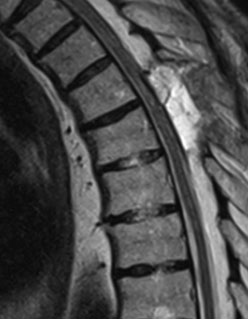

Головний метод діагностики – МРТ, на якому виявляється зміщення спинного мозку та зона притискання спайкою у вигляді «скальпеля». А також, виявляється зона мієлопатії (зона набряку спинного мозку).

Операцію з приводу такої арахноїдальної спайки було виконано у КНП ТОКПНЛ ТОР. Пацієнт 71 рік мав виражений нижній парапарез протягом 4 років, якій поступово наростав.  За 4 тижні до поступлення він перестав ходити. При цьому ноги мимовільно різко рухалися, ніби «підстрибували», навіть уві сні, що заважало йому спати. Такий стан називається – спастичність. Він виникає за рахунок втрати контролю над спінальними рефлексами з боку головного мозку. Сидіти у ліжку пацієнт міг тільки з допомогою, або «обкладаючись подушками з усіх боків». Сили м’язів тулуба вже не вистачало на такі звичайні речі. За кілька днів до операції зник контроль за функціями сечового міхура та кишечника. Лікарі мусили встановити сечовий катетер. На МРТ був виявлений типовий «симптом скальпеля».

Контроль МРТ після операції – добрий. Зона мієлопатії – зменшилася та стала менш інтенсивною.